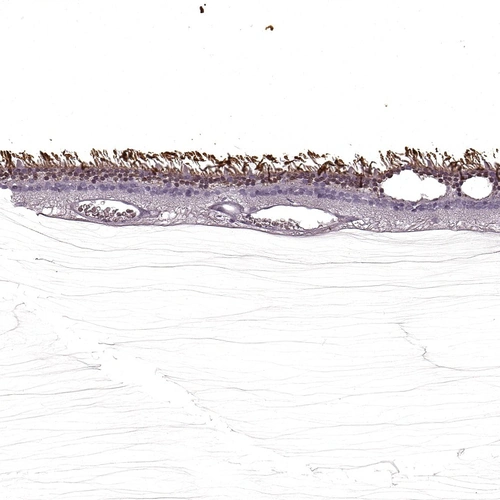

Immunohistochemical staining of human retina shows strong positivity in rod segments.